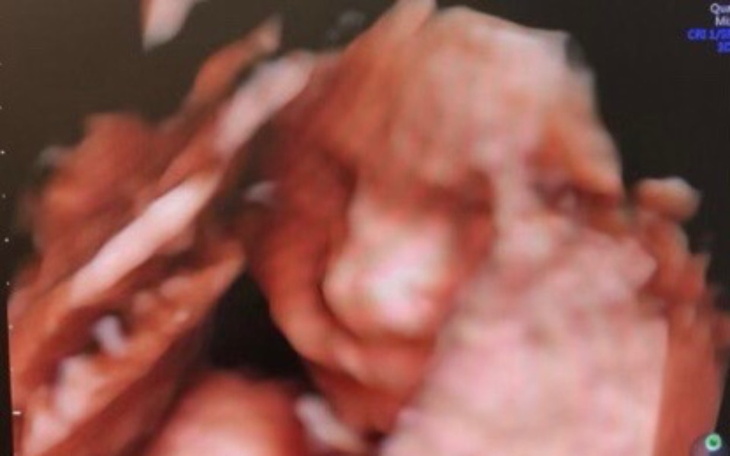

Dzień dobry nazywam się Nikola. Będę młoda samotną mamą, zbieram na wyprawkę dla Niny. Liczy się każdy grosz…Wierze w was że pomożecie z góry dziękuje!